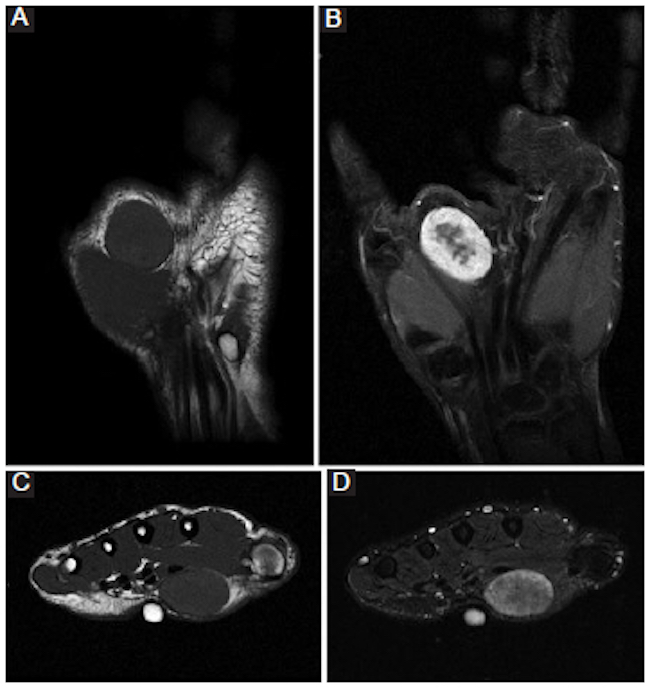

Adicionalmente, se realizó una resonancia magnética (RM) que puso de manifiesto una lesión ovalada bien delimitada, localizada en el tejido celular subcutáneo correspondiente a planos inmediatamente distales y en contacto con los músculos de la eminencia tenar, sin signos de infiltración tisular. En el polo proximal de la lesión se halló una mínima zona de contacto con la superficie cutánea. La lesión presentaba una intensidad de señal isointensa, homogénea en secuencias ponderadas en T1 y heterogénea en T2, con centro redondeado hipointenso y periferia hiperintensa. Tras la administración de contraste paramagnético se constató un realce intenso de la periferia lesional (Fig. 3).

Todos estos hallazgos confirmaron que se trataba de una lesión tumoral sólida situada en las partes blandas superficiales de la mano izquierda, contactando con la piel y con la fascia que recubre la musculatura propia de la eminencia tenar, sobre todo con el tendón del músculo flexor del segundo dedo.